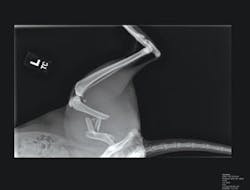

“In the design of existing film-based systems,” says David Gardner, president of Salvador Imaging (Colorado Springs, CO, USA; www.salvadorimaging.com), “a pet is placed on a 17 × 17-in. film plate that is exposed using an x-ray generator. The film is developed and the x-ray viewed on a light console by the physician.” To retrofit these systems, this film plate is replaced with a gadolinium oxide scintillation plate. When subjected to x-ray energy, this plate emits faint green light that must be captured by a digital camera.

“However,” says Gardner, “exposing CCD-based cameras directly within the x-ray path can result in ionization of the silicon dioxide atoms in the layer separating the gate structure from the buried channel in the CCD. This charge is trapped in the dielectric, accumulates over time, and affects the charge-transfer efficiency of the CCD.” Because of this, the Merlin D-Rad system incorporates a 45° mirror that is placed directly under the scintillation plate. “In this way,” says Gardner, “a CCD camera can be mounted perpendicular to the x-ray path and thus can reduce any radiation effects that may occur.”

In the design of RemoteVet’s system, an SI-6M1-FF camera from Salvador Imaging (Colorado Springs, CO, USA; www.salvadorimaging.com) captures reflected images from the scintillation plate. Using a KAF-6303E full-frame image sensor from Kodak Image Sensor Solutions (Rochester, NY, USA; www.kodak.com), the camera is capable of digitizing images at 3072 × 2048 ×12-bit resolution. Captured images are then transferred to a PC-based X64-CL frame grabber from DALSA (Waterloo, ON, Canada; www.dalsa.com).